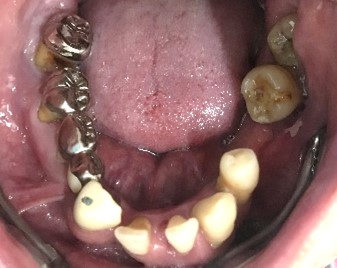

男性Iさん 50代 (マグネット式入れ歯)

主訴

グラグラしている歯がある。歯並びをきれいにし、しっかり噛めるようになりたい。

治療内容

歯周病が進行し深刻な状態でした。保存することができない歯が上4本、下3本ありましたので、抜歯し、残った歯上4本、下7本の歯周病治療を徹底的にし、それらの歯を活用し上下マグネット式総入れ歯を入れました。

所感

治療前は、歯周病が進行し、重度に動揺している歯が4本あり、満足に食事ができない状況でした。マグネット式総入れ歯を装着後は、「なんでも思い通り噛むことができるだけでなく、歯並びもきれいになり、とても幸せです。」と、とても喜んでくださいました。

Before

赤丸は抜歯しました。上4本、下3本